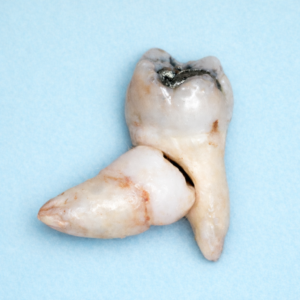

下顎:親知らずが原因で「手前の奥歯」が虫歯になる(第ニ大臼歯の遠心う蝕)

とくに、斜め(近心傾斜)に埋まっている親知らずは、手前の奥歯の後ろ側が磨きにくく、虫歯リスクが上がります。複数の調査で、第ニ大臼歯の遠心う蝕の有病率や、リスクが高い埋まり方(近心傾斜など)が示されています。

↑ このように前に倒れていて、間に汚れが溜まりやすい場合は、注意が必要です